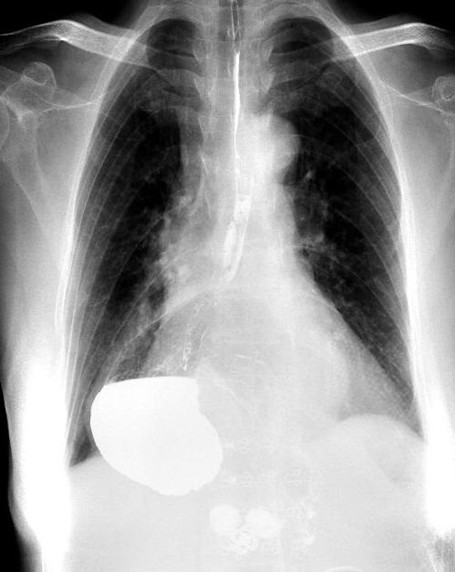

術(shù)前胃“游走”到胸腔。重慶市人民醫(yī)院供圖

接診的胸外科副主任醫(yī)師馬洪飚經(jīng)過詳細詢問及完善相關(guān)檢查,發(fā)現(xiàn)王婆婆所患的疾病叫“食管裂孔疝”,由此造成了胃的“離家出走”,有一部分跑到了胸腔里面,才會出現(xiàn)上述不適。

在完善術(shù)前準備后,胸外科主任馬錚帶領(lǐng)馬洪飚副主任醫(yī)師、張兵兵主治醫(yī)師通過微創(chuàng)手術(shù)不僅將王婆婆游走到胸腔的胃還納到了腹腔,還修補了拳頭大小的食管裂孔,以防止胃再次離家出走。手術(shù)后王婆婆恢復順利,術(shù)前的不適癥狀消失,目前已經(jīng)順利出院。